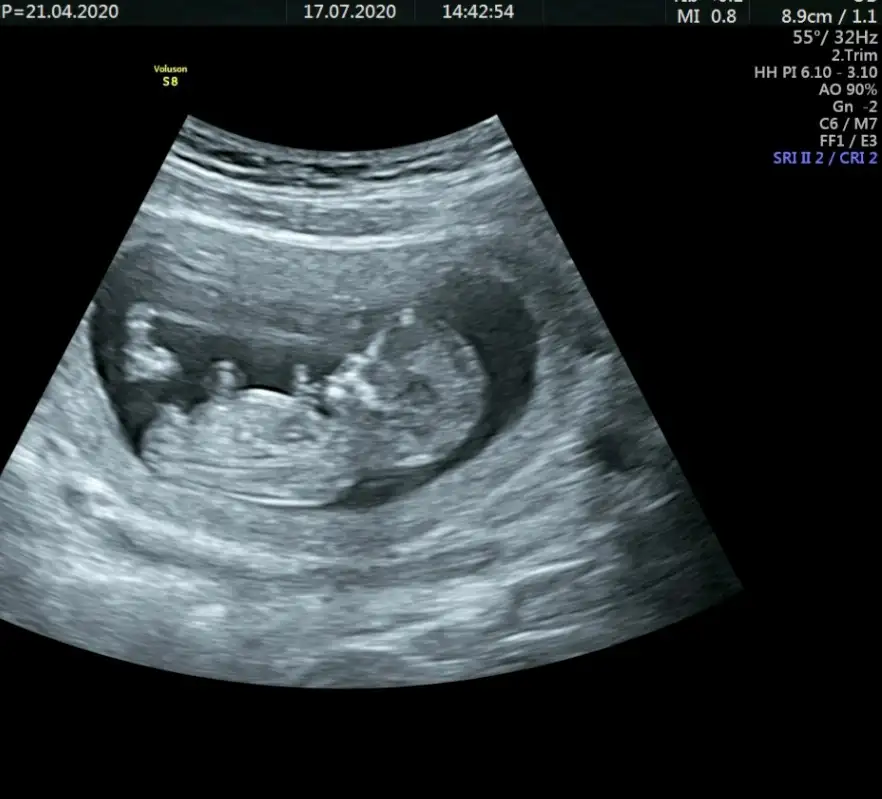

Bunada bakabilir misin :)Dogrudur o zamam emin olamadım nubu ne dik nede paraleldi bebek yan pozisyonda olunca emin olamadım başka usg ile teyit etmek istemiştim hayırlısı olsun sizin için

Erkek gibiBir başka ultrason istemiştiniz bunlar var elimde bacaklarini bağlamışti öylece duruyorduheyecanla yorumunuzu bekliyorumm Ikra meyra